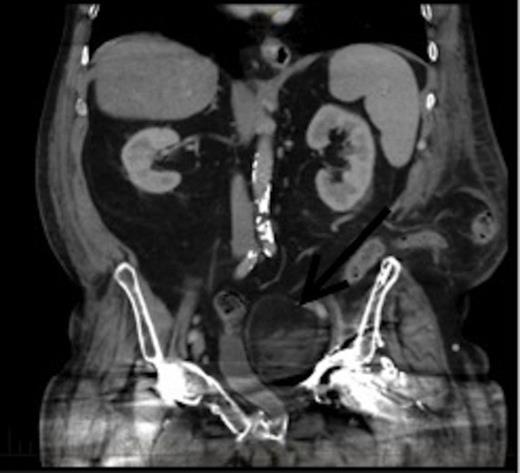

CT coronal view of the lesion demonstrating compression of the bladder. Arrow denotes the EMH lesion

This patient was subsequently discussed at a multidisciplinary meeting, where it was decided that in view of the urinary symptoms and his high operative risk, the mass should be treated with CT-guided radiofrequency ablation using a multi-lined electrode. However, the patient declined treatment and was temporarily lost to follow up after moving interstate. Two years later, he presented to the hospital with bowel obstruction secondary to an incisional lumbar hernia, and the follow up CT scan (Figures 2 and 3) revealed no increase in the size of the mass, and repeat biopsy re-confirmed the presence of EMH. His urinary symptoms remained stable.